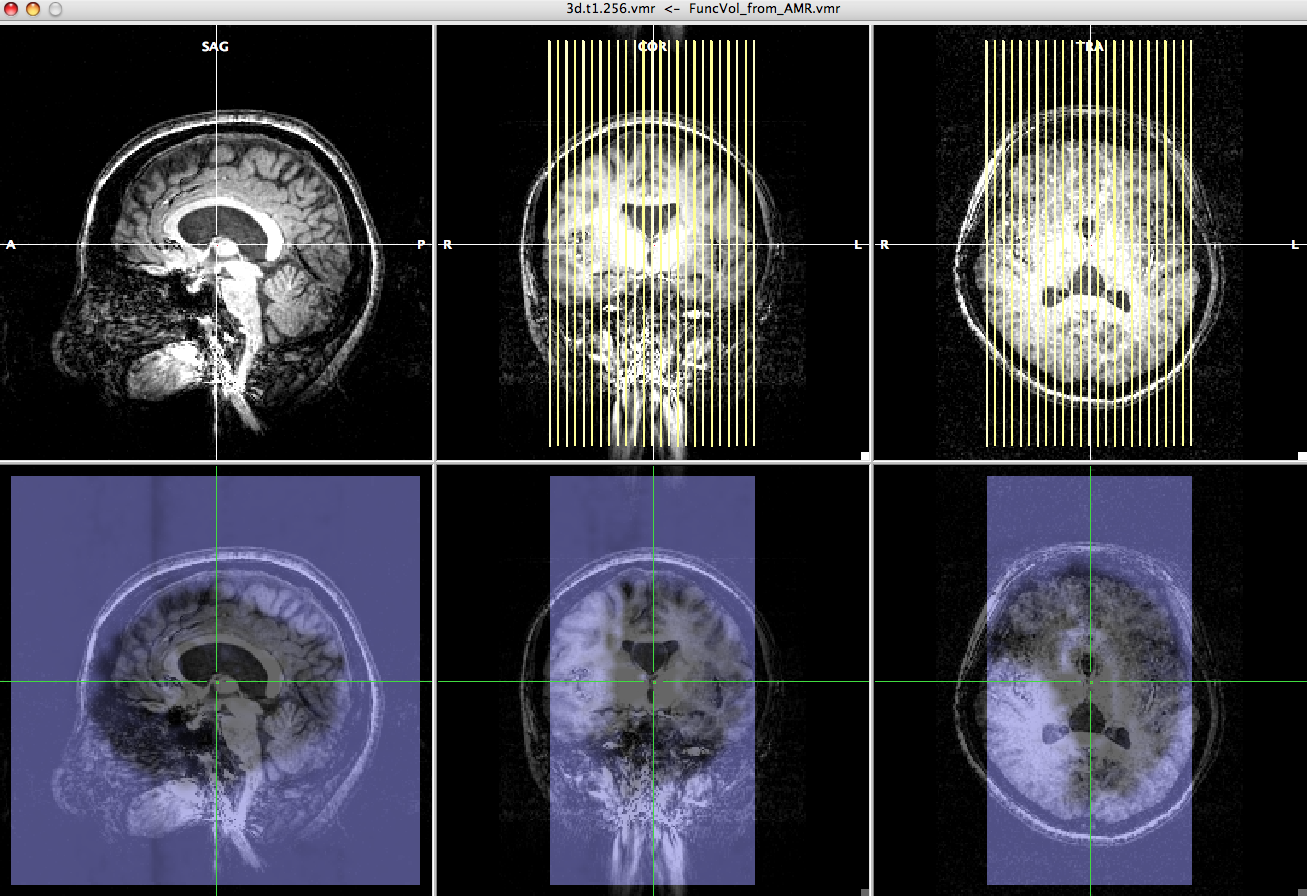

Registration between the epi and high resolution anatomical data†

- Open the anat.high.vmr file.

# Open the anat.high_ACPC.vmr file if you want to check the image in Talairach space.

- Click "Analysis" and select "create 3D-Aligned Time course (VTC) data...".

- Click the "Browse..." to select the epi.fmr file for "Functional slice-based data file (FMR)"

- Select the identify matrix file, epi-TO-anat.high_IA.trf, for "FMR -> VMR coregistration file 1, i.e. header-based (_IA.TRF)".

- Select anat.high_Man.trf file for "FMR -> VMR coregistration file 2, i.e. intensity-based fine-tuning (_FA.TRF)".

Choose "yes" to the dialogue box asking "Do you really want to use it for FMR-TOVMR initial alignment?".

- On the "3D Volume Tools" dialogue, choose "Spatial Transf" and press "Show VTC Vol" and after a while, you will see the image aligned epi image.

- Click the "Blend2" and you can check if the epi image are correctly aligned to anatomy image.